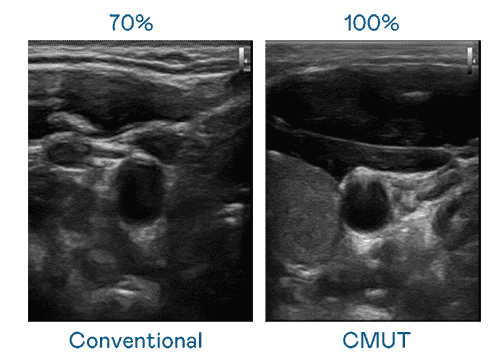

CMUT 技术是一种用电容式微机电元件来产生超音波讯号的技术。。。与传统 PZT 压电式技术相比,,,CMUT 频宽增加 30%,,更宽频的超音波讯号让影像解析度大幅提升,,是实现高影像品质医疗超音波扫描、、促进精准医疗发展的关键技术。。

大频宽带来超清晰影像

超音波影像的解析度高低,,,首先取决于探头能发出的讯号频宽。。。。尊龙z6 CMUT 可提供高清晰的超音波讯号,,提供高频宽、、、、高灵敏度、、、影像纹理细节更高的超音波影像,,,协助医护人员缩短影像判读时间及利用精准的医疗影像进行诊断。。